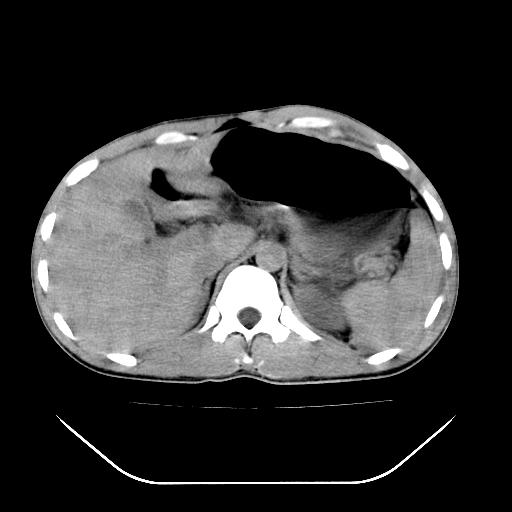

m-25y 高空堕落 12 月5号

12月7号病人尿量200ml/24h 急查双肾ct

左肾挫裂伤并肾周血肿;

肝肾间隙可见液区,建议手术探查;

左肾挫裂伤并肾周血肿

支持 : 左肾挫裂伤并肾周血肿

支持:1、左肾挫裂伤并肾周血肿;

2、少量腹水;

3、左肾旋转不良;

4、反射性肠淤张。